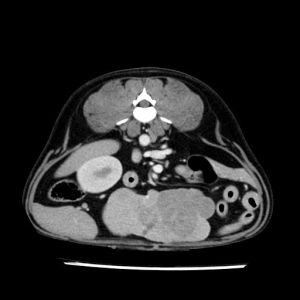

La lesione focale epatica , la ceus,la Tac e il chirurgo .